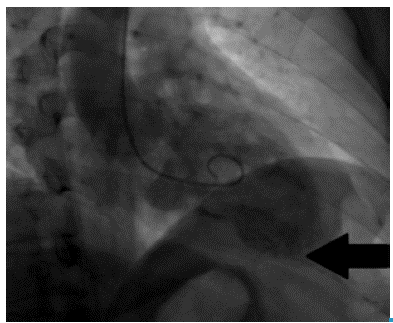

Then, invasive stratification was performed by left ventriculogram and selective coronary angiography (Figure 2 and 3), in which a dominant right coronary system with epicardial coronary arteries, without obstructive lesions and presence of a fistula of the distal anterior descending artery to the left ventricle was found.

Figure 2 shows extravasation of contrast medium into the apical territory irrigated by the anterior descending artery, while, in Figure 3, diagnostic injection on the left coronary artery shows posteroanterior projections (ARC 18°, RAO 25°) (Figure 3A), left oblique with caudal angulation (CAU 20°, LAO 49°) (Figure 3B) and left oblique with skull (CRA 18°, LAO 8°) (Figure 3C). Extravasation of contrast medium is also observed from the anterior descending artery to the left ventricle (black arrow).